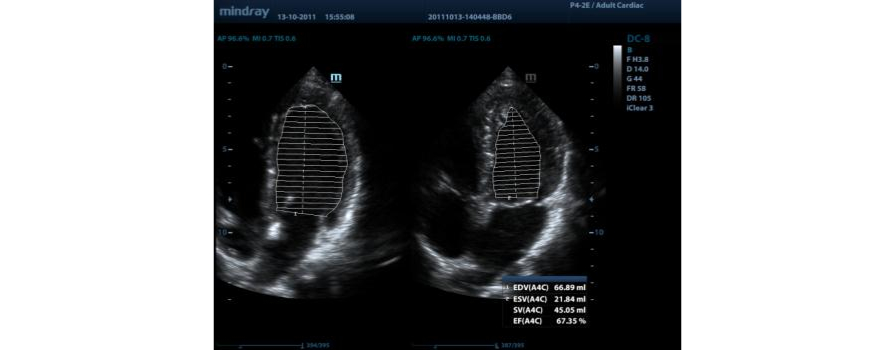

AutoEF

Auto EF ├© un software di intelligenza artificiale che partendo dalla analisi di un cineloop ecocardiografico 2D, riconosce automaticamente i fotogrammi diastolici/sistolici, valuta la funzione del ventricolo sinistro, fornendo il calcolo completamente in automatico della frazione di eiezione e dei volumi diastolici e sistolici